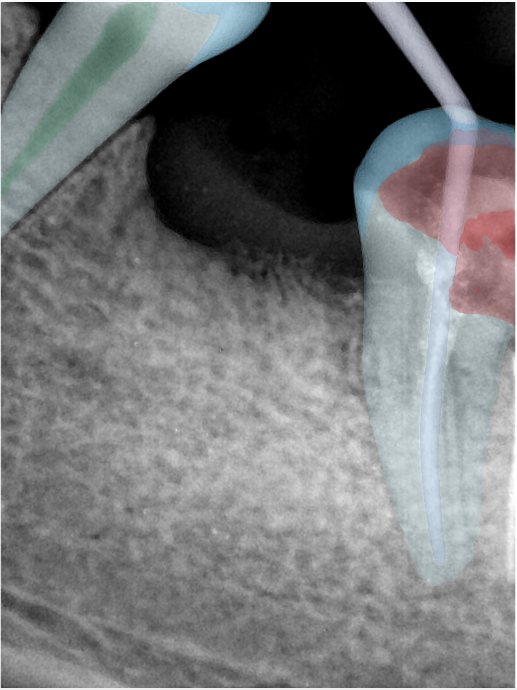

第二版算法问题测试

| 第一版 | 第二版 | 是否解决 | |

|---|---|---|---|

![]() | ![]() ![]() 边角识别有问题 龋齿识别不全 牙髓识别不全 | ![]() | 解决 |

![]() | ![]() 边角识别有问题 识别信息有误 自查(牙冠识别不全) | ![]() | 解决 |

![]() | ![]() ![]() 边角识别有误 大范围填充识别遗漏 | ![]() | 解决 |

![]() | ![]() 识别信息不全 | ![]() | 解决 |

![]() | ![]() ![]() 边角问题 牙胶识别不全 牙冠识别不全 | ![]() | 解决 |

![]() 换图片 | ![]() | ![]() 牙冠部分稍微白了一些就识别成小范围修补,部分判断异常 | 部分解决,修复类略敏感,牙冠部分稍微白了一些就识别成小范围修补,部分判断异常。 |

![]() | ![]() ![]() 牙冠识别不全 牙髓不全 根尖炎龋齿识别有误 | ![]() | 解决 |

![]() | ![]() | ![]() | 解决 |

![]() 换图片 | ![]() | ![]() | 解决 |

![]() | ![]() 牙冠识别有误 | ![]() | 解决 |

![]() 换图片 | ![]() ![]() 边角识别有误 | ![]() 修复类敏感 | 部分解决,图像过白,导致修复类判断异常。 |

![]() 换图片 | ![]() 牙冠识别不全 | ![]() 修复类敏感 | 部分解决,图像过白,导致修复类判断异常 |

结论:修复类出现了不鲁棒的情况,后续需要加入轮廓的扩充数据进行增强。